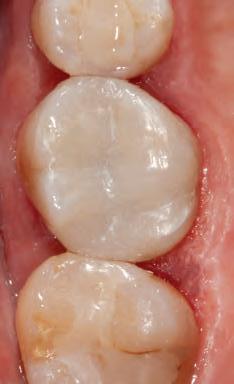

DISTO-OCCLUSAL CLINICAL CASE